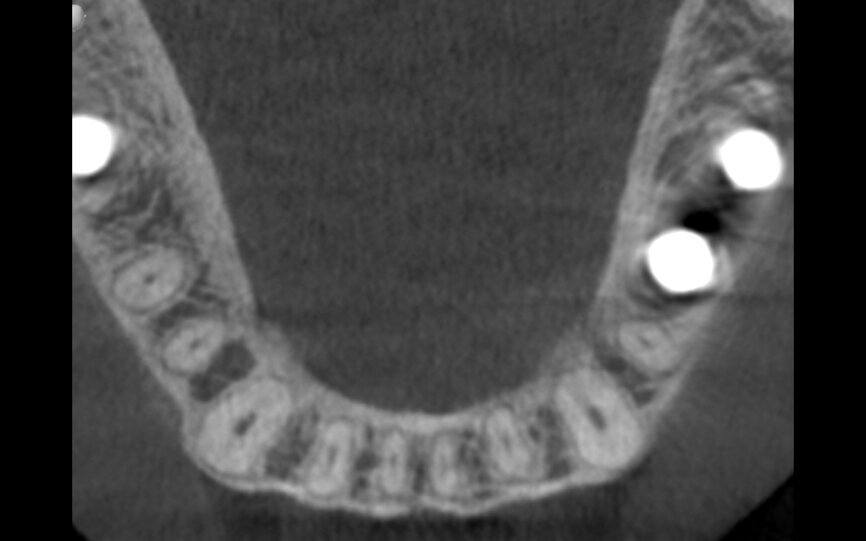

Fig. 11: The two-year follow-up post-op CBCT scan.

The two-year follow-up postoperative cone beam computed tomography (CBCT) scan (Figs. 11 & 12), as well as the clinical photographs, illustrated the bone level, the buccal bone volume achieved and maintained over the period. Also, it was possible to see that the gap distance, radiographically, appeared to have been filled with bone. It was surprising also to see that bone level was well above the implant–abutment junction, maybe in response to a very efficient maintenance of a zero micro-gap at the junction owing to this BioBlock (BTI Biotechnology Institute) one abutment, one time concept, providing a virtual one-piece implant.